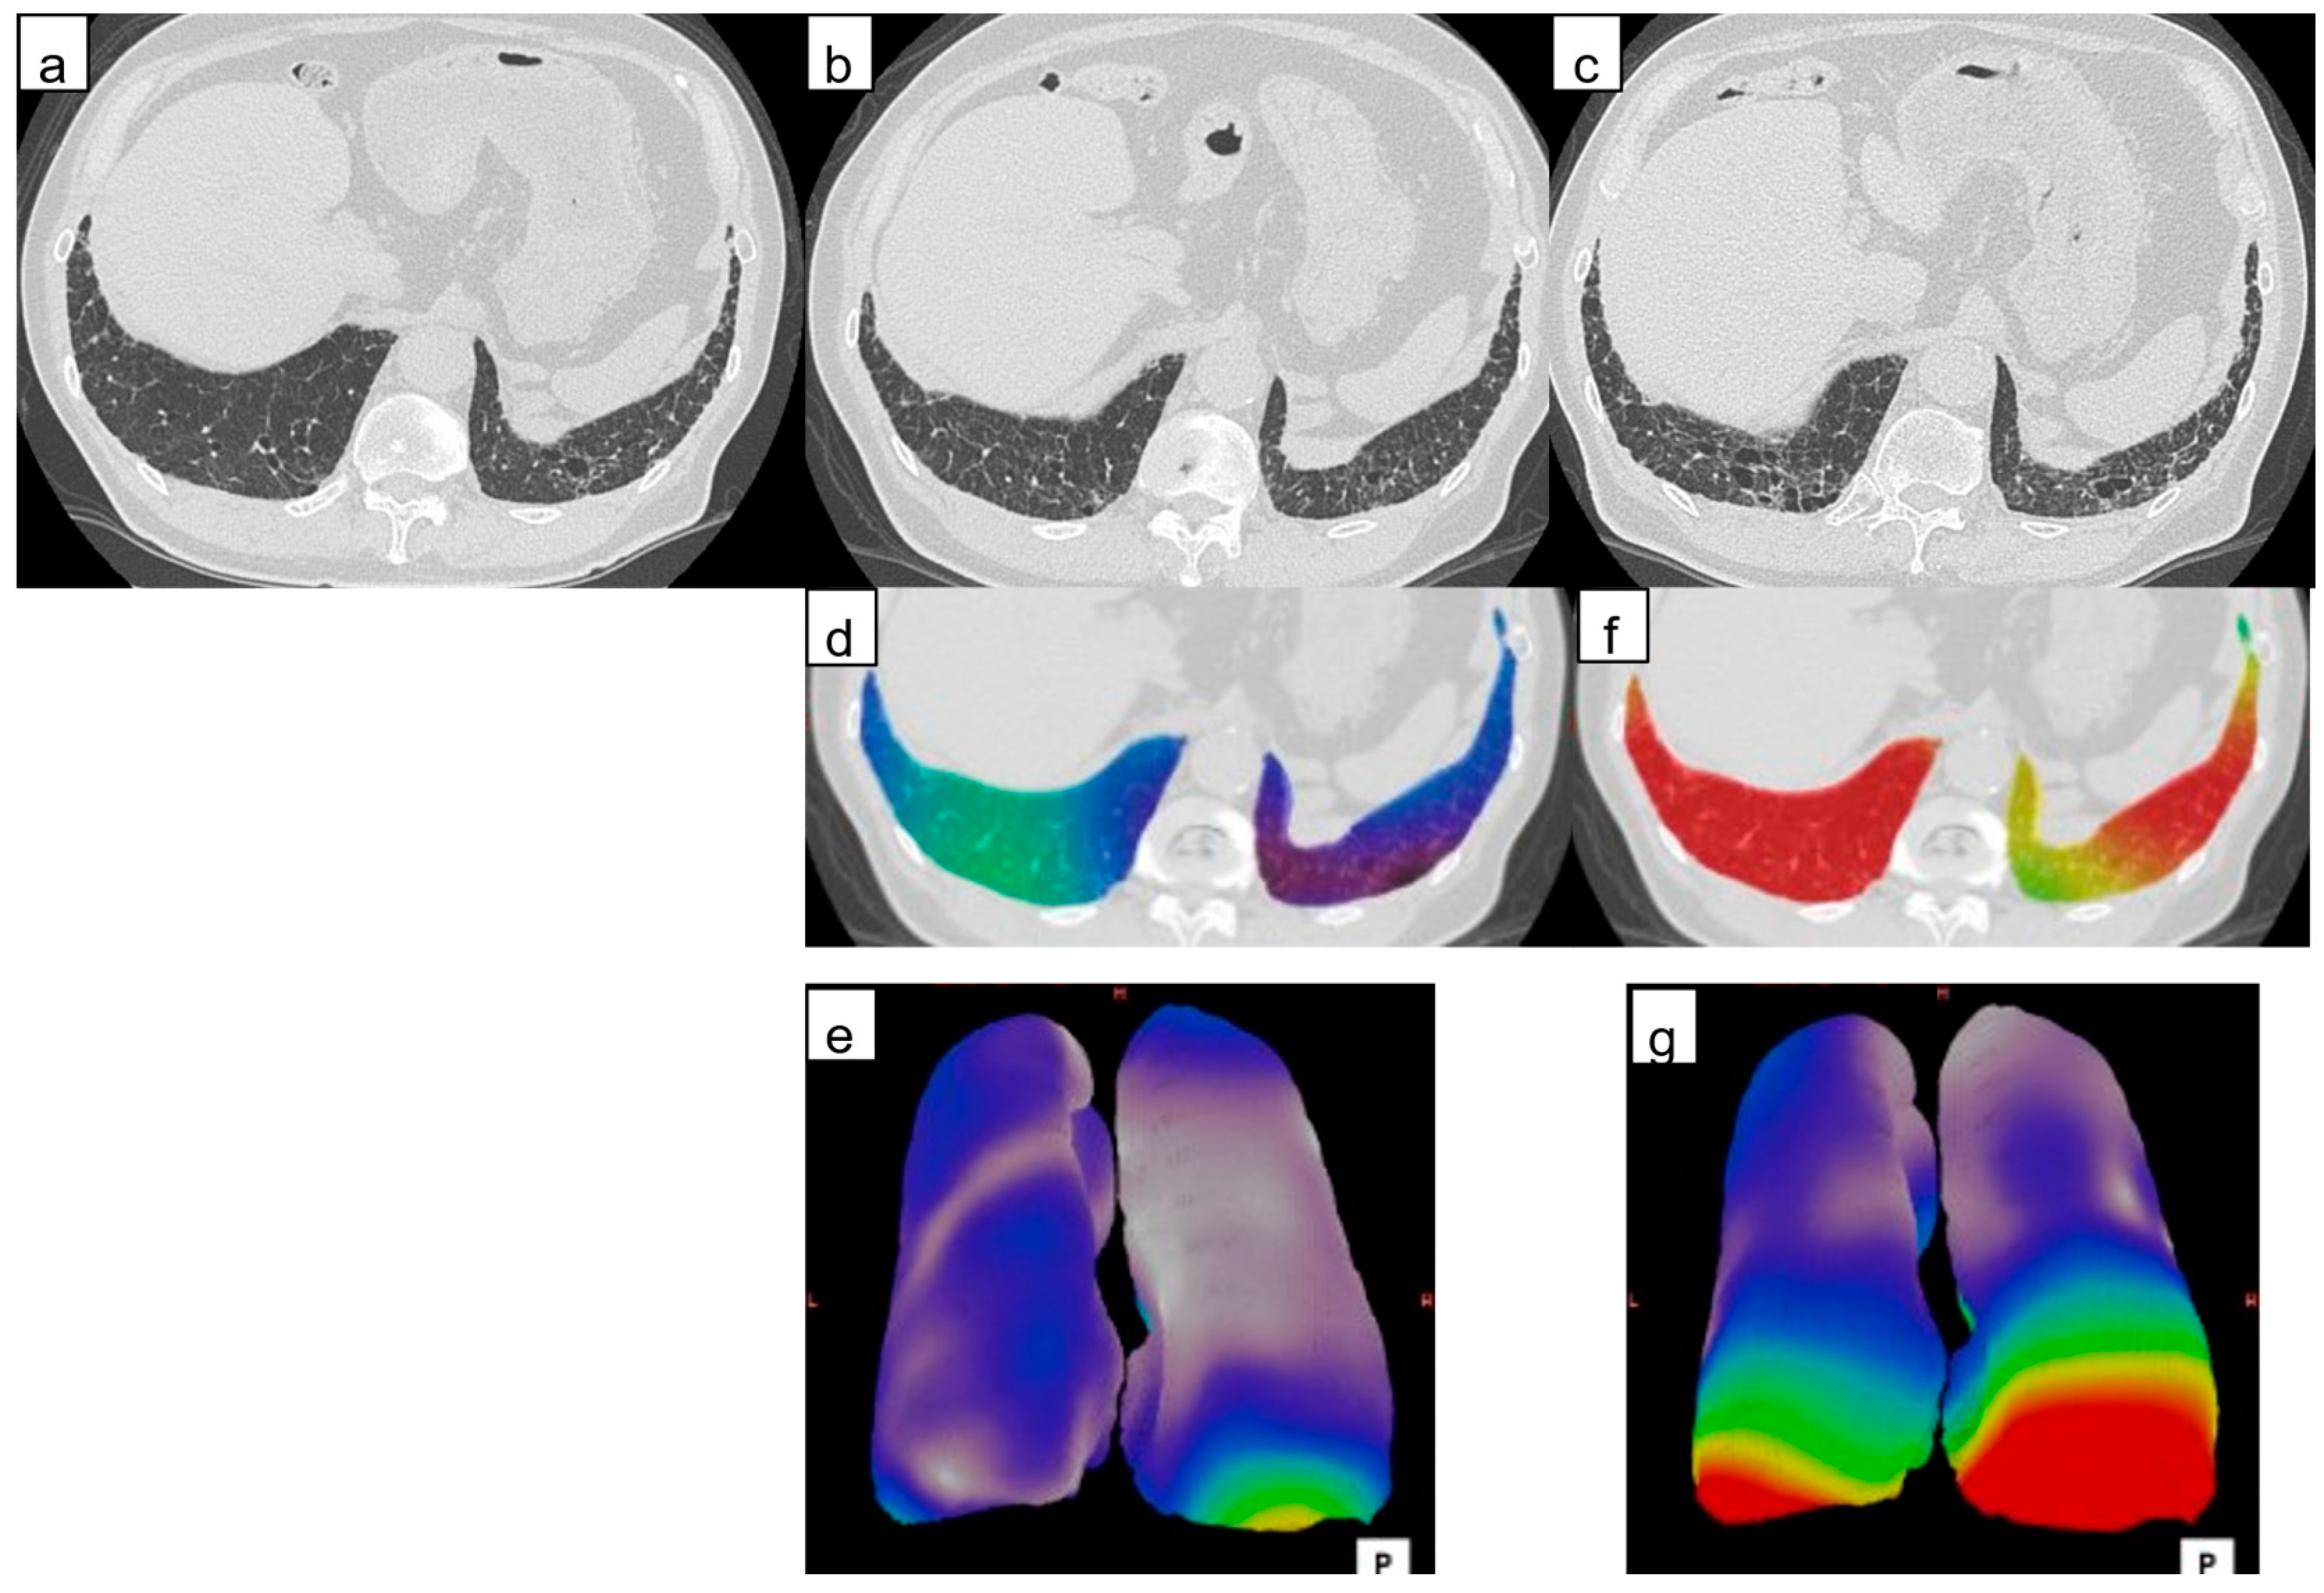

Figure 5.

Computed tomography (CT) images of a 77-year-old man with idiopathic pulmonary fibrosis and three-dimensional average displacement (3D-AD) color maps. (a) Initial CT image of the lung base showed subpleural interstitial abnormality. (b) Follow-up CT image after one year shows a little increase of subpleural lesions in the posterior areas of the right lung base. (c) Follow-up CT image after two years shows obvious progression of fibrosis at the lung base. (d,e) The 3D-AD color map shows yellow scale in the posterior areas of the right lung base. (f,g) Color map of the 3D-AD shows a greater deviation (red in the color map) observed. Local displacement of peripheral structures is evident before lung abnormalities and lung volume loss are clearly visible at the follow-up CT.

The recent guideline indicates radiological evidence of disease progression in UIP pattern fibrosis as an increased extent or severity of traction bronchiectasis and bronchiolectasis, new ground-glass opacity with traction bronchiectasis, new fine reticulation, increased extent or increased coarseness of reticular abnormality, new or increased honeycombing, and increased lobar volume [1]. An increase in lesion volume on CT and a decrease in lung volume can be objectively measured using computer-based software. The change in lesion extent, however, is not large in UIP-pattern fibrosis; for example, a previous report showed the annual change in fibrotic lesion volume was 2% of the predicted total lung capacity of patients with IPF without antifibrotic drug use, and 0.14% in those using antifibrotic drugs [28]. This may be because UIP-pattern fibrosis is accompanied by alveolar collapse (volume decrease) [29], and in smokers, emphysematous lung (volume increase), and these simultaneous phenomena will mask volume loss, leading to underestimation of the progression by the lesion volumetric analysis. We stress that the 3D-AD color map could demonstrate local parenchymal displacement in patients with a small amount of increase in the fibrotic lesion extent, as shown in Figure 5. We believe the 3D-AD color map could help raise awareness of fibrosis progression in such mild cases. In the recent clinical practice guideline [1], progressive pulmonary fibrosis (PPF) is newly defined as at least two of three criteria (worsening symptoms, radiological progression, and physiological progression) occurring within the past year with no alternative explanation in patients with an ILD other than IPF. In addition to computer-based quantitative assessments of the fibrotic lesion extent, 3D-AD of annual HRCT could be useful to promptly detect radiological progression of PPF and possibly influence prognosis.